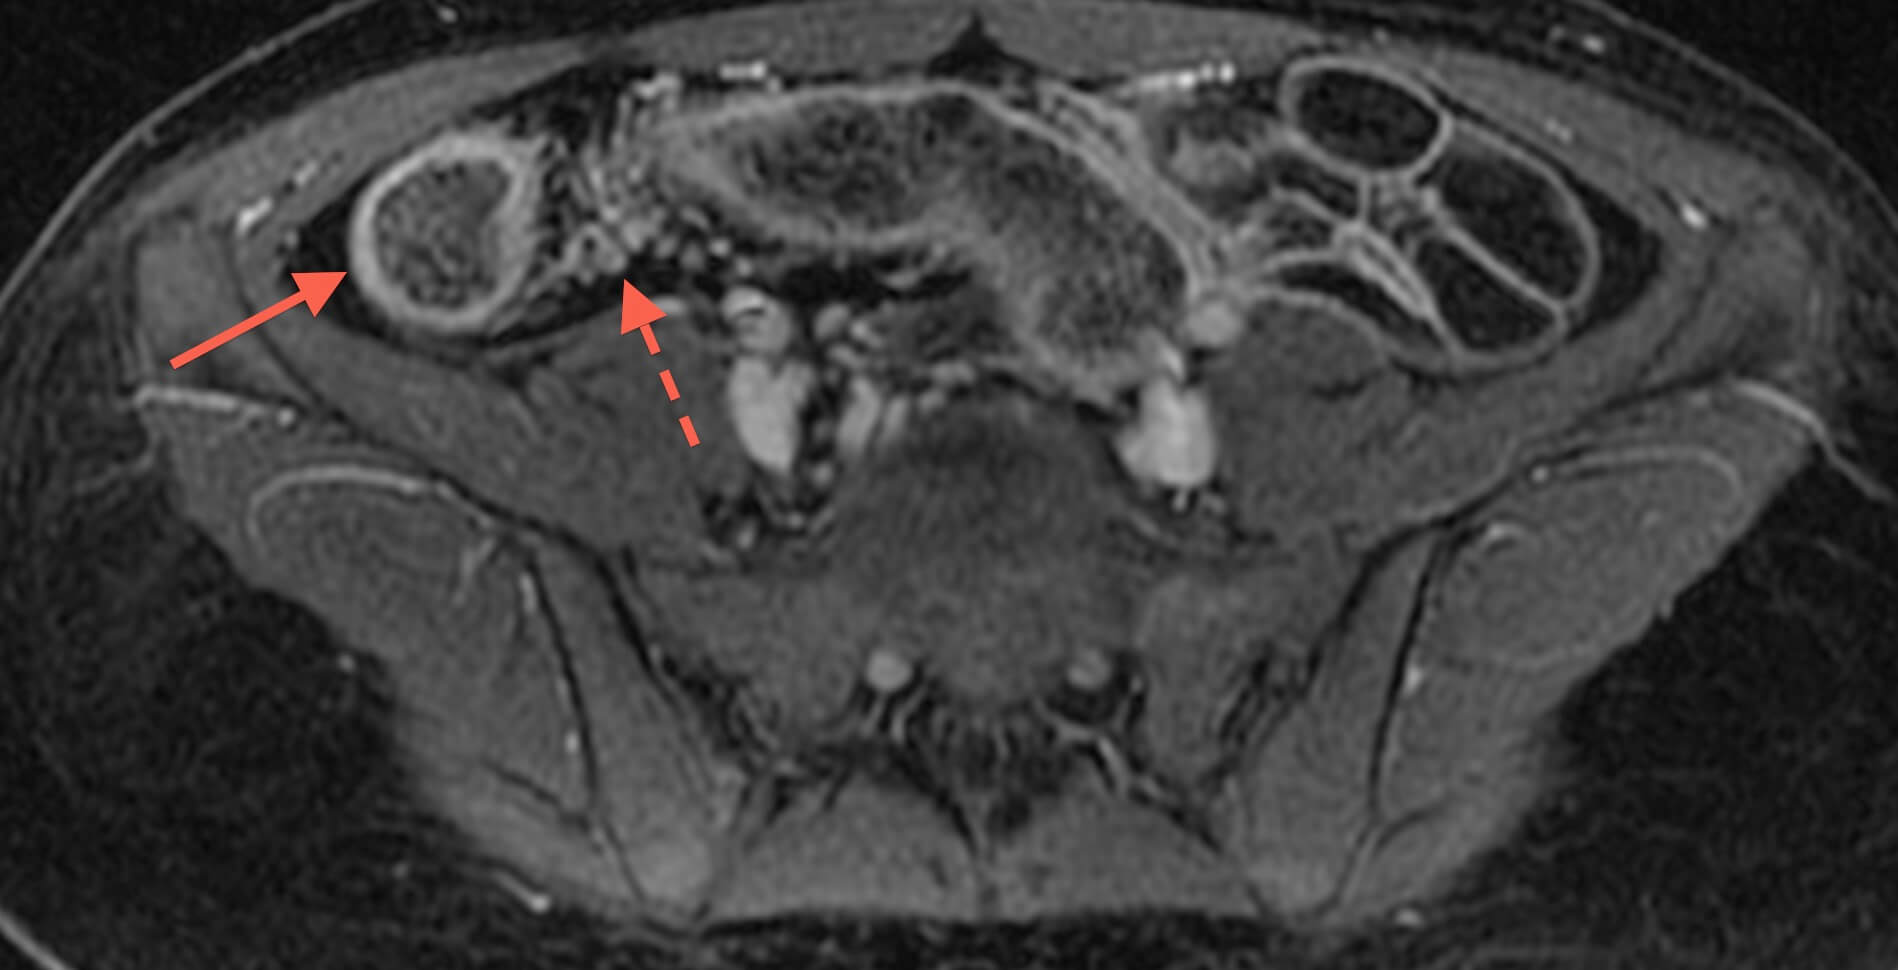

MR enterography is valuable for determining extent of inflamed bowel, discriminating between active inflammation and chronic fibrosing disease, detecting fistulae, and detecting strictures. Additionally, MRI can provide excellent delineation of the course of perianal fistulas, including relationships to sphincters and levators.

Before undergoing MRI to evaluate the bowel, one drinks a little over one quart of a fluid that helps to distend the bowel, and an intravenous catheter is placed so that intravenous contrast can be administered.